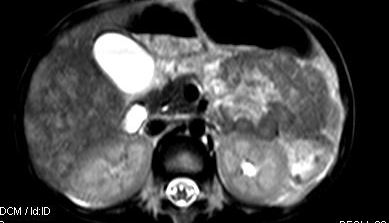

标题: V0176(MRI):小儿发热,肝脾大,肝内病变 [打印本页]

标题: V0176(MRI):小儿发热,肝脾大,肝内病变

5岁,2006年8月曾行阑尾炎手术,现发热半年